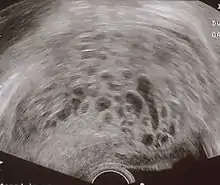

Transvaginal ultrasonography showing a molar pregnancy

The diagnosis is strongly suggested by ultrasound (sonogram), but definitive diagnosis requires histopathological examination. On ultrasound, the mole resembles a bunch of grapes ("cluster of grapes" or "honeycombed uterus" or "snow-storm").[14] There is increased trophoblast proliferation and enlarging of the chorionic villi, and angiogenesis in the trophoblasts is impaired.[15]